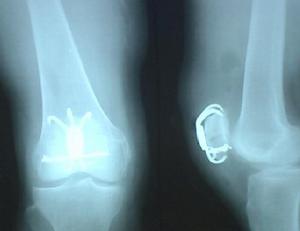

(1)骨折:鎖骨骨折,肩鎖關節脫位,肩關節脫位,肱骨外科頸骨折,肱骨幹骨折,肱骨髁上骨折,肘關節脫位,橈骨頭半脫位,前臂雙骨折,橈骨下端骨折;髖關節脫位,股骨頸骨折,股骨轉子間骨折,股骨幹骨折,髕骨脫位,髕骨骨折,膝關節韌帶損傷,膝關節半月板損傷,脛骨平台骨折,脛腓骨幹骨折,踝部骨折,踝部扭傷,足部骨折;脊柱和骨盤骨折。